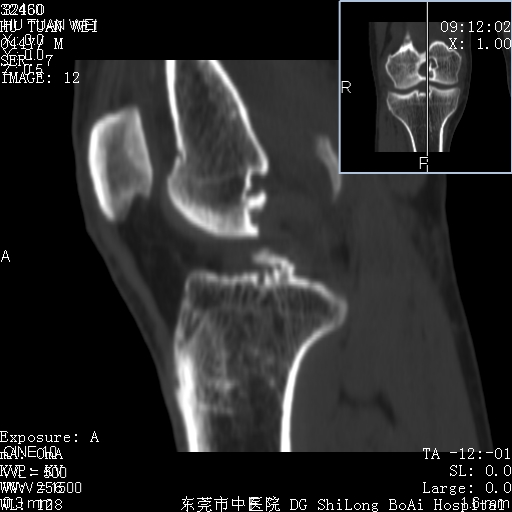

中年男性,膝韧带损伤术前检查!其他病史不清粗,不是我接手病人、且出院了!

1、股骨下段囊状膨胀性病变,边缘硬化明显,内多个残留骨棘呈多房型改变,囊腔密度较高无钙化,膝关节滑膜囊增厚,密度增高,关节腔少量积液。考虑:邻关节囊肿、退变性囊肿(软骨下囊肿)、着色性绒毛结节性滑膜炎、abc、骨巨、良性纤维组织细胞瘤等鉴。虽然年龄偏大,部位于骨端,但有外伤史,本人还是倾向于动脉瘤样骨囊肿(abc)可能性大。邻关节囊肿及软骨下囊肿次之考虑。

2、胫骨髁间棘撕脱骨折,交叉韧带损伤可能;

3、关节退行性改变。

病理结果:色素沉着绒毛结节性滑膜炎

感谢反馈病理结果!本病为慢性关节病变。以关节滑膜高度增生、绒毛结节形成伴含铁血黄素趁着为特点。病因:有炎症、肿瘤、外伤关节出血、代谢障碍、变态反应及感染等学说。增强扫描呈关节腔内单个或多个强化的软组织结节影或滑膜不规则增厚伴关节积液为本病的特征性表现。